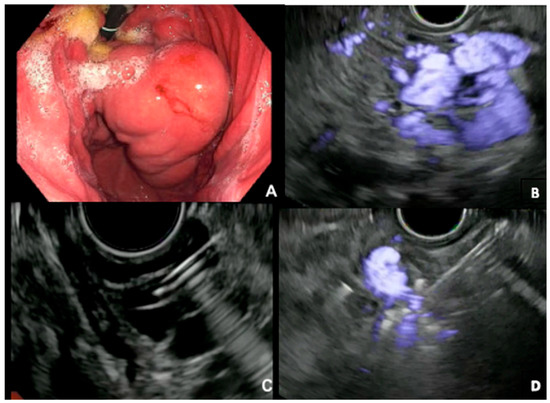

2.2.1. EUS-Guided Gastric Variceal Coiling

- Robles-Medranda, C.; Valero, M.; Nebel, J.A.; de Britto, S.R., Jr.; Puga-Tejada, M.; Ospina, J.; Muñoz-Jurado, G.; Pitanga-Lukashok, H. Endoscopic-ultrasound-guided coil and cyanoacrylate embolization for gastric varices and the roles of endoscopic Doppler and endosonographic varicealography in vascular targeting. Dig. Endosc. 2019, 31, 283–290. [Google Scholar] [CrossRef] [PubMed]

- Bhat, Y.M.; Weilert, F.; Fredrick, R.T.; Kane, S.D.; Shah, J.N.; Hamerski, C.M.; Binmoeller, K.F. EUS-guided treatment of gastric fundal varices with combined injection of coils and cyanoacrylate glue: A large U.S. experience over 6 years (with video). Gastrointest. Endosc. 2016, 83, 1164–1172. [Google Scholar] [CrossRef]

- Bazarbashi, A.N.; Wang, T.J.; Jirapinyo, P.; Thompson, C.C.; Ryou, M. Endoscopic Ultrasound-Guided Coil Embolization with Absorbable Gelatin Sponge Appears Superior to Traditional Cyanoacrylate Injection for the Treatment of Gastric Varices. Clin. Transl. Gastroenterol. 2020, 11, e00175. [Google Scholar] [CrossRef]